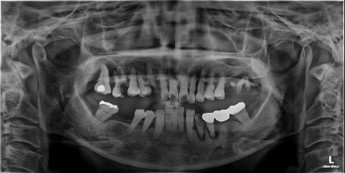

상악동거상술 후 전악임플란트 2025-09-26 |

오늘은 심한 충치로

환자분의 치조골 상태, 치주 상태가 너무 안좋은 상태였기 때문에 |

상악골 뼈가 부족해 임플란트가 어려울 때상악동 거상술

상악동 거상술은 위턱뼈(상악골)의 골량이 부족할 때 시행되는 뼈이식 수술입니다.

상악동 점막을 들어올리고 인공 뼈를 채워, 임플란트가 안전하게 식립될 수 있도록

뼈의 높이와 두께를 보강하는 고난이도 술식입니다.

전체 치아를 상실했을 때전악 임플란트

전악 임플란트는 치아가 전혀 없거나 심한 구강 질환이 있을 때도

전체 보철물을 제작하고 임플란트를 잇몸 뼈에 식립하여

자연치아와 거의 같은 기능과 미용 효과를 되살려 줍니다.